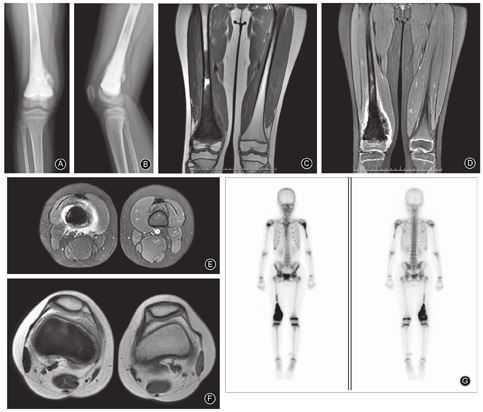

患者于2月14日在局麻下行右股骨远端穿刺取活检术,术后病理报告示可见肿瘤性成骨,符合普通型骨肉瘤。依据新辅助化疗方案,手术前化疗2个月,手术后化疗4~6个月,顺铂120~140 mg/m2、表柔比星20~30mg/m2静脉点滴,化疗两个疗程。于2019年5月8日行右股骨远端瘤段切除人工假体重建术,术后右股骨正位、侧位X线片可见肿瘤切除彻底,假体位置合适,并保留了胫骨近端骨骺;病理切片可见肿瘤性成骨(图3)。

右股骨瘤段切除肿瘤假体置换术后影像学表现及病理组织学图片 A,B 右股骨正位、侧位X线片可见肿瘤切除彻底,假体位置合适,并保留了胫骨近端骨骺 C,D 股骨瘤段切片,可见肿瘤性成骨,符合普通型骨肉瘤(C,×4;D,×20)

于2019年5月22日行左肱骨近端骨肉瘤瘤段切除、灭活、再植、钛板内固定术,术后左肱骨正位、侧位X线片可见瘤段灭活彻底,固定位置合适;病理切片可见瘤性成骨,符合骨肉瘤表现(图4)。

左肱骨近端骨肉瘤瘤段切除、灭活、再植、钛板内固定术后影像学表现及病理组织学图片 A,B 左肱骨正位、侧位X线片可见瘤段灭活彻底,固定位置合适 C,D 股骨瘤段切片,可见肿瘤性成骨,符合骨肉瘤表现(C,×4;D,×20)

第二次手术后2周患者出现颈部疼痛、活动受限,再次入院行颈椎MR检查示C2-4椎体周围及椎间可见团块状不规则形(图5)。胸部CT扫描示双肺多发异常信号,考虑转移瘤。手术部位无局部复发现象发生。依据身体状况又给予顺铂及表柔比星方案的化疗,效果欠佳。逐渐出现、全身恶病质、呼吸不畅,于2019年7月28日死亡。

第二次手术后2周颈椎MR检查矢状面和水平面T2WI示C2-4椎体周围及椎间可见团块状不规则形